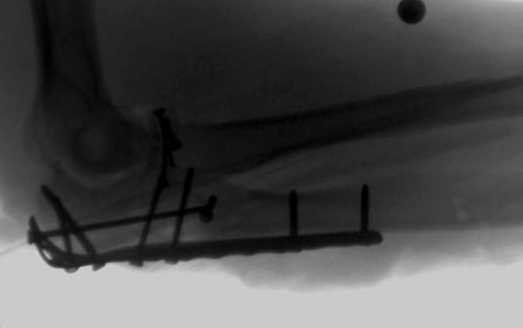

Снимки вот еще какие есть (наши лаборанты пытались сделать что то)

Good day dears colleagues! You presentated only one x-ray proection - lateral- of elbow.Accorden this I thing that this isn't avulsion fracture of olecranon,as usually can to see.This is Monteggia like fracture with subluxation of radial head.If

you can show AP x-ray or more more better CT elbow

I will more sure.Any way more imported of all normal long of ulna.So my recomendation ORIF proximal ulna by LCP - allow normal long by bridging, without attention to continues cortex but attention to articular surfase. On operation examen of radial head,becouse my sence isn't without damage.Operation by standart approach.